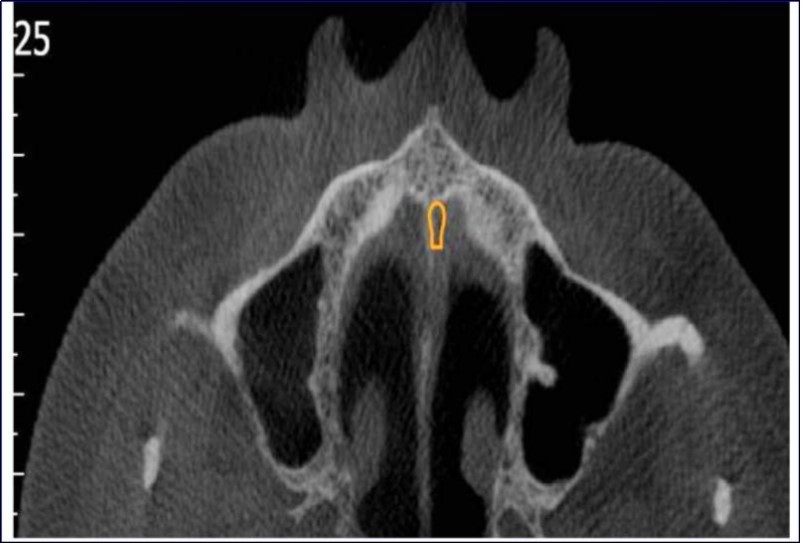

Sinus augmentation procedures were carried-out in 17 patients seeking implant options for oral rehabilitation including 10 for direct and 10 of indirect procedures (n=20, 10 direct and 10 indirect). The study comprised of 43% females and 57% males with a mean age of 46.07 years. A total of 17 patients (20 segments) satisfying the above criteria requiring placement of implants in atrophic maxilla/ increased pneumatisation of the maxillary sinus were selected for the study. The patients were informed about the study including the use of the synthetic graft material and their approval was sought before their inclusion in the study. A written informed consent was obtained from each of the participating patients. For each patient, a detailed case history was taken including chief complaint, history of presenting illness and medical history and personal history. A thorough clinical examination, including systemic and regional examination, was done. Patients with sinus pathology, previous sinus surgeries, chronic smokers, patients under 18 years of age, and with underlying systemic conditions which contradicts any surgical procedures were excluded from the study. The type of sinus lift was decided based on the pre-operative residual bone height evaluated radiographically. The residual bone height was recorded using CBCT scan and a computer based software where the measurements were made from the crest of the ridge till the sinus floor lining. Indirect sinus augmentation was done in patients with a bone height of <9mm but more than or equal to 5mm. Patients with a bone height of less than 5mm were taken up for direct sinus augmentation. The period of edentulousness varied from 6 months to 12 months. Apically tapered, commercially pure titanium implants (Life Care Devices Private Limited Mahim, West Mumbai, India) were used for patients undergoing indirect sinus augmentation. The length of implant was 8, 10, and 11.5 with diameters of 3.5, 4.0, and 5 mm respectively. Patients in the category of direct augmentation underwent the lateral approach procedure and augmentation with an alloplastic graft material. Implant placement was done after 6 months as the second stage procedure. The patients were assessed clinically at immediate post-operatively, and at 1 week, 1 month, 3 months, and 6 months post-operatively. Radiographic assessment for bone height was done pre-operatively and at 6 months post-operatively using cone beam computer tomography. In this comparative study, the measurements were tabulated and statistically analyzed to evaluate the difference in increase in bone height between direct and indirect sinus augmentation procedures radiographically. Orthopantomographs (screening tool) were taken to rule-out other pathologies and as a part of initial assessment. CBCT scans were assessed for pre-operative and post-operative bone height, bone width and bone density. The CBCT scans were obtained from Kodak 9300 which is a hybrid machine using a CS3D imaging software and flap panel detector sensor with exposure parameters of 90 KVp and 10 mA and resolution of 90 microns. The cross sections were made 1mm apart. (Image 1, Image 2, Image 3) The bone height measured pre-operatively using CBCT considered the pre-operative bone height as a measurement taken from the crest of the ridge till the sinus floor and post-operatively, from the crest till hyper-density evident apically. These measurements were standardized as a computer software drawing tool was used. Bone width was taken as the bucco-palatal width at three intervals- at the crest, 3mm from the crest and 6mm from the crest. Bone density was assessed visually by the width of trabecular pattern and were classified based on Misch‘s classification.4 Another additional bone density tool used was the pixel values (the gray scale values) obtained on the CBCT scan, although not reliable, and comparison done pre-operatively and post-operatively. The pixel values contained were a mean of three measurements obtained along the residual bone corresponding with the bone width levels.

Image 2.Axial section of CBCT showing sinus septae